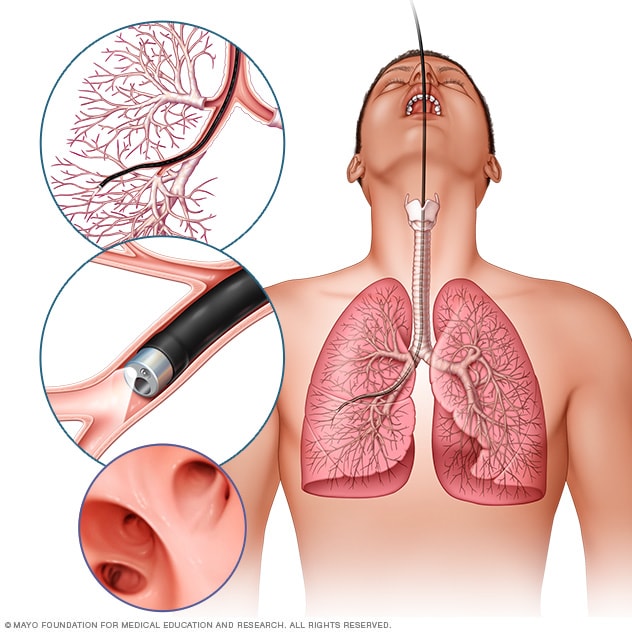

اختبار بسيط يكشف الإصابة بسرطان الرئة صورة الكونسلتو

سرطان الرئة التشخيص والعلاج Mayo Clinic مايو كلينك

من خلال فحص بسيط للإصبع يمكن الكشف المبكر للإصابة بسرطان الرئة صورة تركيا الآن